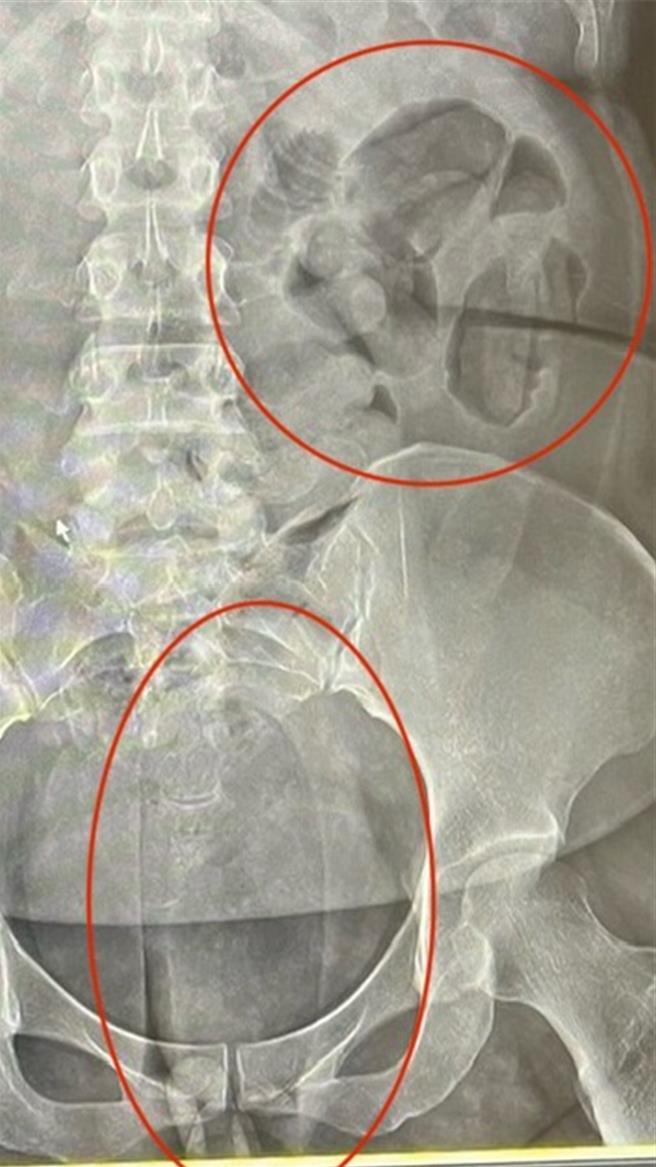

内政部警政署保安警察第三总队查获外籍女子以人体运毒方式夹带毒品海洛因与古柯碱等毒品重达5公斤,市值约3500万元。图为夹带毒品X光照。(保三总队提供/徐佑升基隆传真)

警方调查指出,5月30日桃园国际机场查获2名泰国籍犯嫌夹藏海洛因,合计毛重1755.6公克。其中A女吞下50颗海洛因胶囊;B女则吞下55颗,两人亦均另以私密处夹藏,因此总重量超过1.7公斤,于人体运毒的案件量体很大,相当罕见,警方立即成立专案小组,比对案情、地点等关系深入追查。

检警调查,该跨境运毒集团以保险套及热缩膜等层层紧密包装海洛因,压缩成椭圆形球状外观,使其易于塞入体内或口服吞入。而根据目前市场价格,本次查获毒品总价值高达3500万元,若流入市面将造成重大危害。